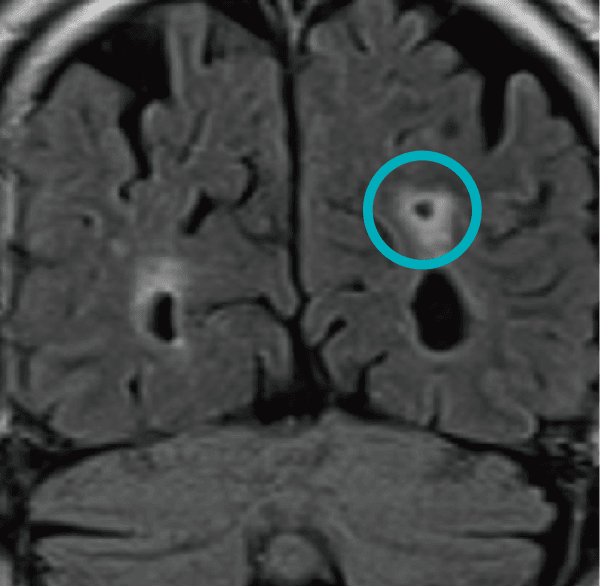

陳旧性ラクナ梗塞

ラクナ梗塞はごく細い動脈が詰まることで生じる小さな脳梗塞です。症状のないラクナ梗塞は、脳卒中の危険因子です(危険比率3.7倍)。これ自体を治療することはできません。背景に高血圧や動脈硬化など他の病気や喫煙習慣があることがあり、治療可能なものは治療しましょう。病変については、経過観察をおすすめします。万一症状が出現した際は、直ちに医療機関を受診してください。